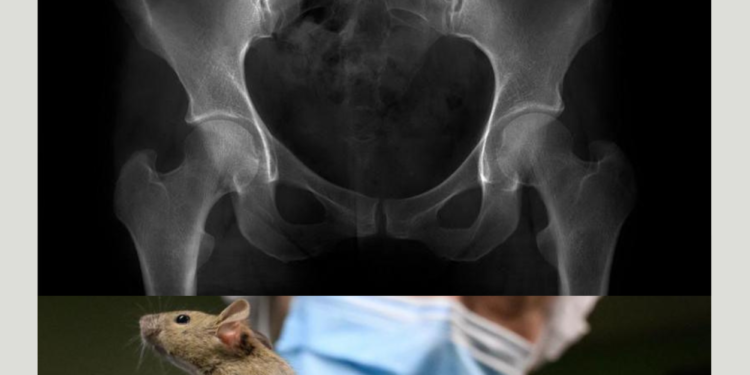

நாம் சுமார் 2.5 கோடி ஆண்டுகளுக்கு முன்பு நமது வாலை இழந்தோம். அதன் பரிணாம எச்சமாக நாம் இன்னும் கோசிக்ஸ் (coccyx) என்று அழைக்கப்படும், நமது முதுகுத்தண்டின் கீழ்முனையில் இருக்கும் ஒரு சிறு முக்கோண வடிவிலான எலும்பினைச் சுமக்கிறோம்.

இந்த விளைவை ஆராய இக்குழு இந்த மரபணுச் சூழ்நிலையை எலிகளில் உருவாக்கிப் பார்த்தது. இதனால் எலிகள் வால் இல்லாமல் பிறக்கும் வாய்ப்புகள் அதிகரித்தன.

ஆனால் அக்குழு வேறு விசித்திரமான ஒன்றையும் கண்டறிந்தது. TBXT மரபணுவின் வடிவத்தை மட்டும் பிரித்து விலக்கி ஒரு எலி உருவாக்கப்பட்டால், அது மனித ஸ்பைனா பிஃபிடாவைப் (spina bifida) போன்ற ஒரு நோயுடன் பிறக்கிறது. இது முதுகெலும்பு மற்றும் முதுகுத் தண்டு கருப்பையில் சரியாக வளர்ச்சியடையாமல், முதுகெலும்பில் ஒரு இடைவெளி இருக்கும் நிலை.

நமக்கு வால் எலும்பு ஒரு பரிணாம எச்சமாக இருப்பதைப் போலவே, வால் இல்லாததை உறுதிப்படுத்தும் மரபணுவின் மாற்றத்திற்கு ஸ்பைனா பிஃபிடாவை நோய் ஒரு அரிய தொடர்ச்சியாக இருக்கலாம் என்று இந்த ஆராய்ச்சிக் குழு கருதுகிறது.